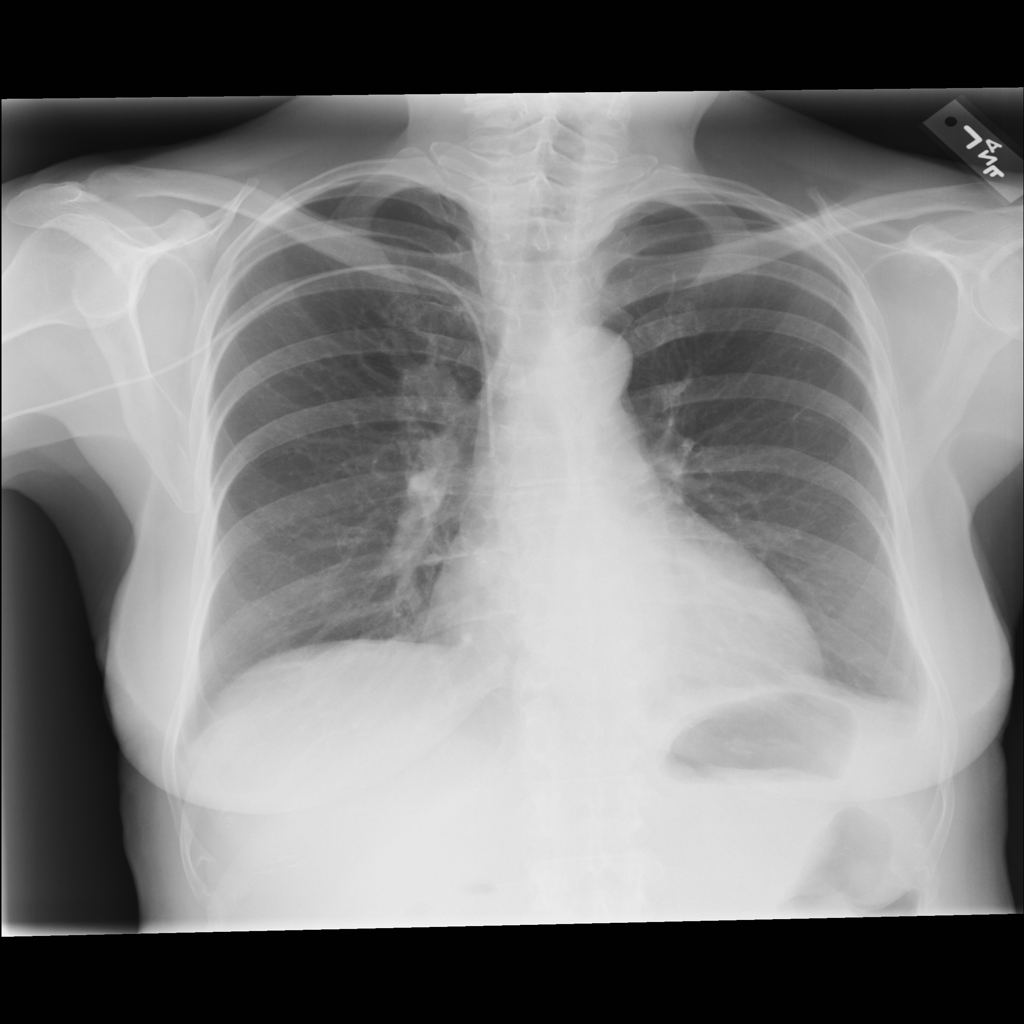

Mass

A mass is a larger focal opacity or lesion seen on the image. It is a descriptive finding that can have several causes and usually needs more imaging or clinical context to characterize.

PAT-D7A5 · IMG-000Mass

PAT-D7A5 · IMG-000

PA